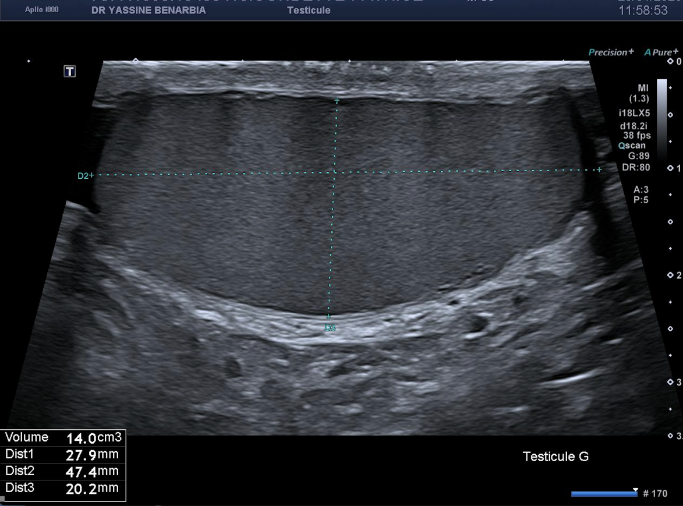

L'échographie retrouve des testicules de morphologie, taille et vascularisation strictement normales bilatéralement. Les épididymes sont également normaux, sans signe d'inflammation. Le Doppler couleur montre une vascularisation testiculaire symétrique et physiologique.

L'exploration de la région inguinale est donc réalisée révélant une hernie inguinale gauche indirecte avec un sac herniaire contenant des anses grêliques lors des manœuvres de Valsalva. Le collet herniaire mesure 20 mm lors de l'hyperpression abdominale. La hernie est parfaitement réductible et ne présente aucun signe de complication (péristaltisme conservé, paroi digestive fine, vascularisation normale au Doppler).